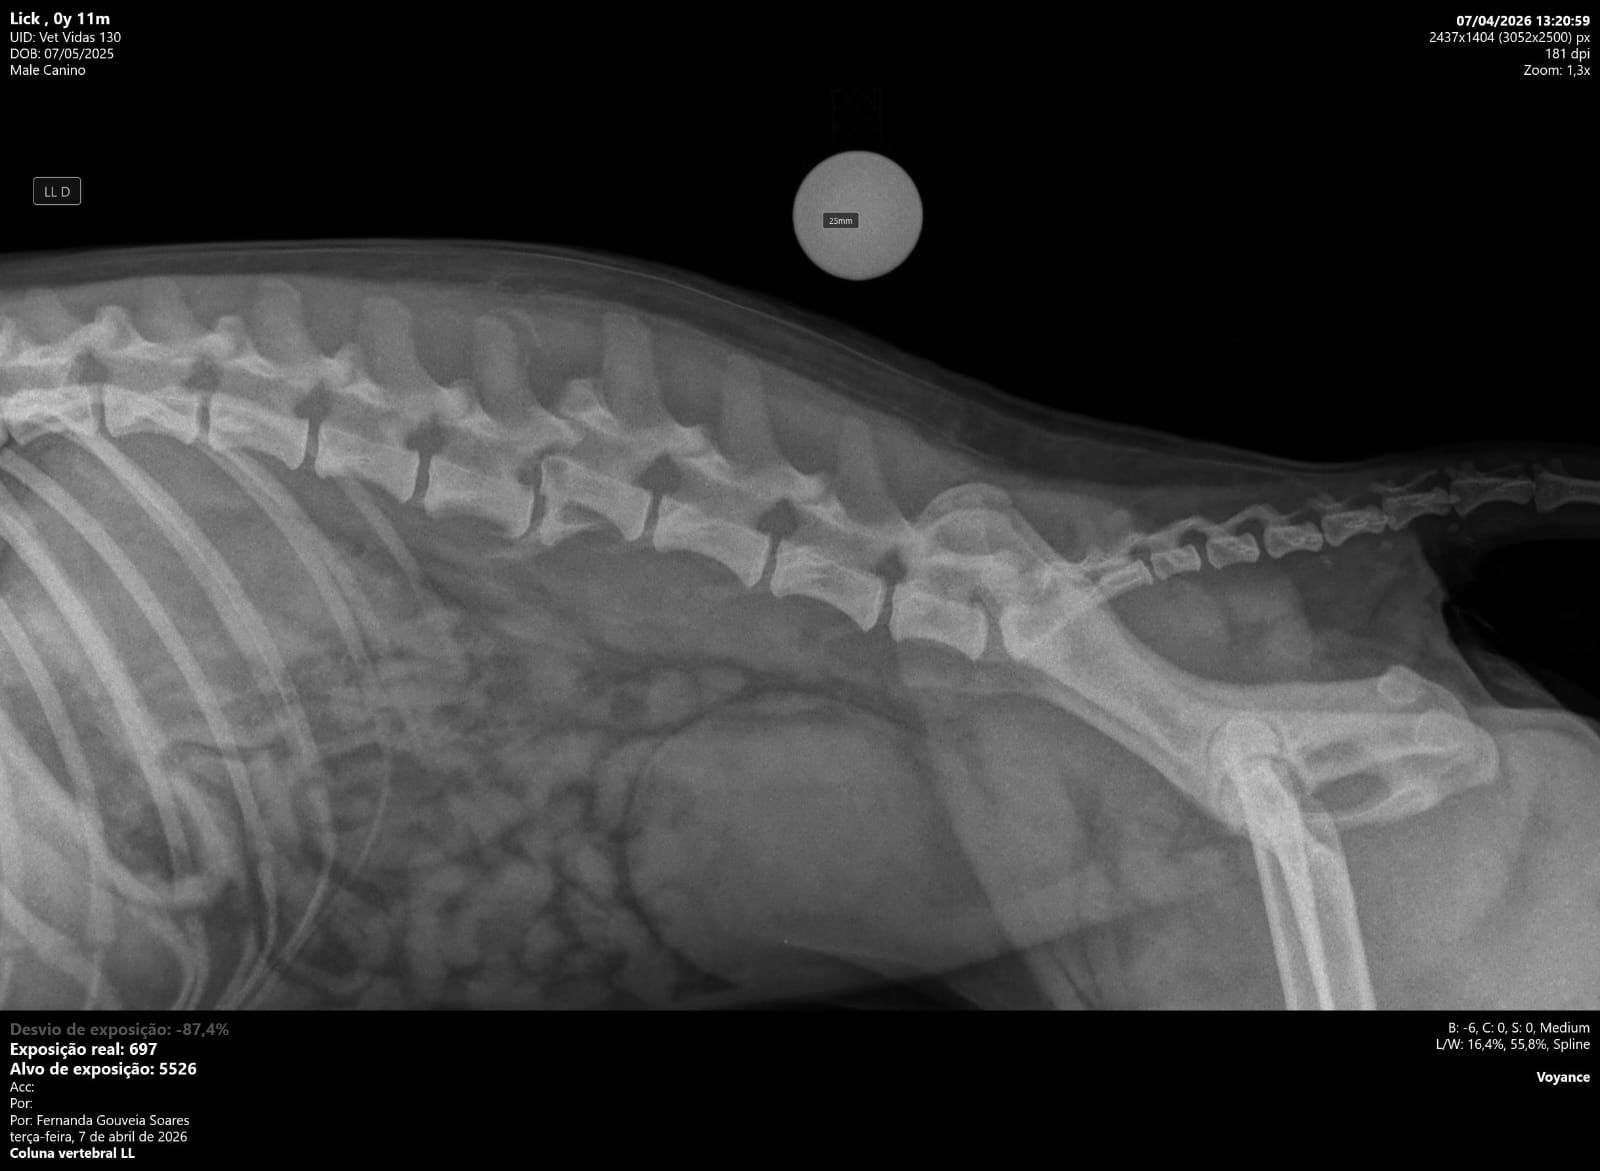

Lucky passou por exames e uma cirurgia na coluna, e agora precisa continuar o tratamento e recuperação.

Lucky é um cachorro cheio de amor que recentemente sofreu uma grave complicação de saúde e precisou passar por uma cirurgia delicada na coluna.

Ele precisou de atendimento urgente, exames, internação e acompanhamento veterinário constante.